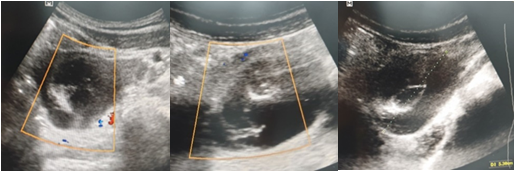

Case 3: A 26-year-old patient presented with severe pain, nausea and vomiting, and amenorrhea. Her pregnancy test was positive. Pelvic ultrasound showed right ovarian cyst fluid with septum negative Doppler at 7 weeks (Figure 3). She was given treatment with progesterone for 4 weeks. She had regression of the cyst after 11 weeks.

Figure 3 Pelvic ultrasound showing ovarian cyst >5cm with septum negative Doppler and gestational sac at 7 weeks.